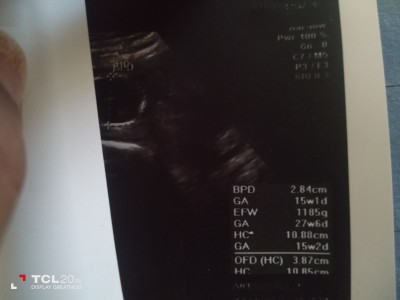

Kilosu nerde yazıyor normal mi

Gebelik haftası

15

Kac haftaliksin cnm eger 15 haftaliksan kilosu yanilistir 27 haftaliksanda dogrudur

EFW olan kilosu 15 haftaya göre aşırı fazla ben 24.haftada gittiğimde bile 637 gram dı.Senin 15. Haftada 1185 olman hiç normal değil.Yada yanlışlık var bu kadar kilo olmaz.

18 haftadan once kilo.kısmı genelde çok yazıliyor 3 gebeligimdede oyle.oldu 18den sonra ölcumler rahat oldugu icin tahmini kilolar daha uyumlu oluyor 21+1 deyiz 360 gr dedi bugün doktor

Canım kesinlikle yanlıştır 15 haftada bu kilo olmaz yada bı sorun vardır doktorun demiştir zaten bu kiloda olamaz

Canım kilosu 1 kilo 185 gram haftasına göre bence çok normal.

27 haftaysa normal canim ama değilsen yanlış 15 hafta da bu kadar kilolu olması imkansız :) EFW yazan yer kilosu canım